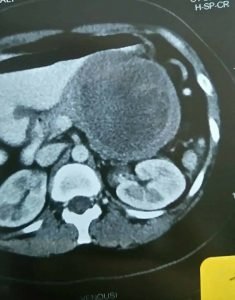

و أيضاً هناك إهتمام منا بنوعية من أورام البنكرياس وهي أورام البنكرياس الكيسية Pancreatic Cystic Neoplasmas وهذه الأورام تكون علي هيئة أكياس في البنكرياس وهناك اهتمام عالمي بها في الآونة الأخيرة نظراً لزيادة معدل إكتشاف هذه الأورام الكيسية وذلك بإستخدام وسائل التشخيص بالأشعة الحديثة مثل الأشعة المقطعية والأشعة بالرنين المغناطيسي والأشعة بالموجات فوق الصوتية بالمنظار مع إمكانية أخذ عينات بواسطة إبرة دقيقة من هذه الأورام لتحليل السائل والخلايا والأنسجة الموجودة في هذه الأورام.

وهناك أنواع مختلفة من هذه الأورام الكيسية فعلي سبيل المثال هناك الاورام الكيسية المصلية Serous Cystic Neoplasmas وهناك الأورام الكيسية المخاطية مثل Mucinous Cystic Neoplasmas وكذلك Intraductal Papillary Mucinous Neoplasmas وهناك الأورام الصماء الكيسية Solid Cystic Pseudopapillary Neoplasmas وهناك أورام أخري لايتسع المجال هنا لذكرها.

وعلاج هذه الأورام يحتاج إلى التشخيص الدقيق وإجراء العملية الجراحية المناسبة حسب نوع وحجم ومكان الورم وحسب نوعية الخلايا الموجودة في الورم سواء كانت حميدة أم خبيثة ودرجتها، وكذلك حسب عمر المريض أو المريضة والحالة الصحية.